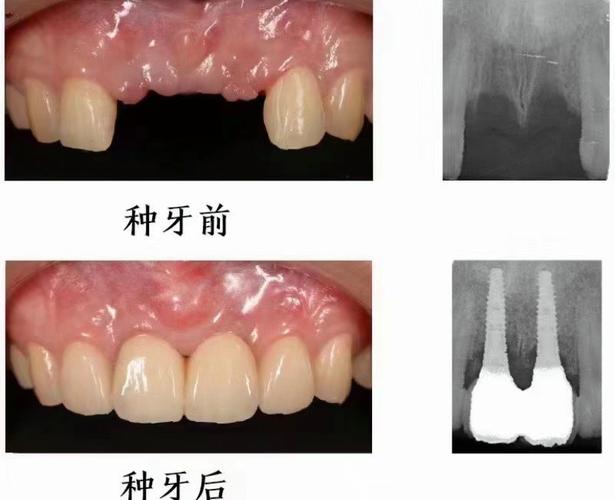

(图片来源网络,侵删)- 高水平医院众多: 广州拥有众多实力雄厚的大型三甲医院(如中山大学附属口腔医院、南方医科大学南方医院、广东省口腔医院等),其口腔科/种植中心拥有顶尖的专家团队、先进的设备(如CBCT、口内扫描仪、3D打印导板等)和丰富的临床经验,尤其擅长处理复杂病例。

(图片来源网络,侵删)- 价格范围广: 种植牙费用受多种因素影响:种植体品牌(如瑞士Straumann、瑞典Nobel Biocare、德国Ankylos、韩国Osstem/Dentium等)、牙冠材料(全瓷、烤瓷)、是否需要植骨、上颌窦提升、是否使用数字化导板、医院等级、医生资历、诊所定位等,在广州,单颗种植牙的总费用(含种植体、基台、牙冠)从几千元到两三万元甚至更高都有可能。